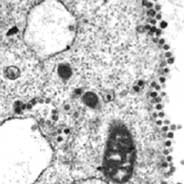

The causative virus was soon identified as a coronavirus, and it was characterized by early May. The results indicate that the SARS coronavirus is not related closely to any of the previously characterized coronaviruses but forms a distinct group within the genus Coronavirus. It is approximately equidistant from all previously characterized coronaviruses, just as the existing groups are all equidistant from one another. It was concluded that: “the genetic distance between the SARS coronavirus and any other coronavirus in all gene regions implies that no large part of the … genome was derived from other known viruses. The … genomic sequence does not provide obvious clues concerning the potential animal origins of this pathogen”; and that: “The genome of SARS-Coronavirus has several unique features that could be of biological significance. The short anchor of the spike-protein, the specific number and location of small open reading frames (ORFs), and the presence of only one copy of the PLPpro provide a combination of genetic features that readily differentiate this virus from previously described coronaviruses” (Rota et al., 2003).

Phylogenetic analysis |